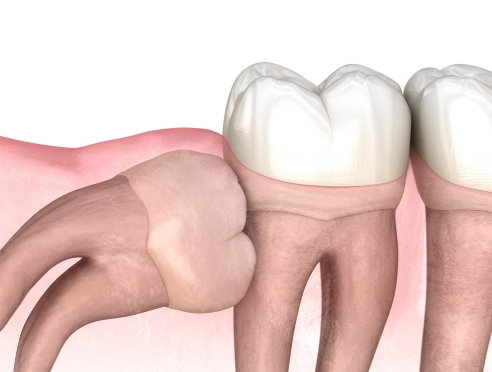

在通过锥形束CT精细确认智齿方向,

神经位置及与邻牙关系后,

仅在

确有必要的情况下才进行拔除

采用最大程度减少组

织损伤的方式来降低负担,

帮助患者更轻松地完成术后恢复